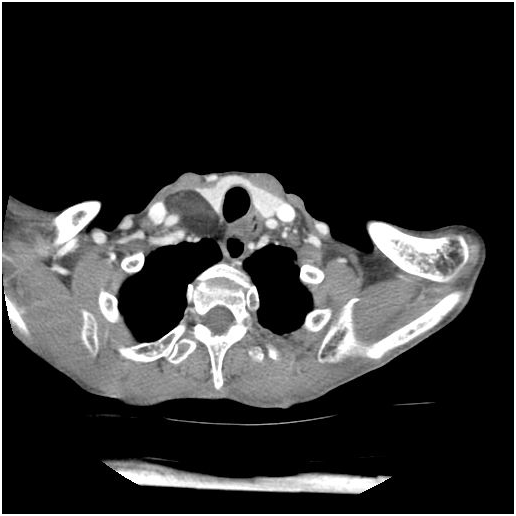

Fibrolipomas have been defined as a subtype of lipomas that are benign soft tissue tumors according to the WHO classification [1]. They differ from classic lipomas with being connective tissue bands involved among the mature adipose tissues [2]. Fibrolipomas have been described in the esophagus, pharynx, colon, trachea and larynx [3,4]. Rarely may they be seen in the oral cavity and in the maxillofacial area. In the oral cavity, fibrolipomas are most commonly found in the buccal region followed by tongue, lower lip and the parotid region; respectively [5,6]. Retropharyngeal space is an area extending from the skull base to the mediastinum, located between the middle and deep layers of the cervical fascia. It contains a small amount of fatty tissue and chains of lymph nodes especially at the suprahyoid level [7]. Lymph nodes and lymphatic channels are the main components of this space [8,9]. Tumors of the retropharyngeal region are extremely rare. The most commonly seen mass is in a form of inflammatory or tumorous lymph node enlargement [7]. Reported cases of lipomas in this region are less than 40 in the literature [10]. Whereas retropharyngeal fibrolipoma was reported by Huang in a 17-year-old male patient in 2008 and by Ganakalyan et al. [12] in a 2-year-old pediatric patient in 2008 [11] (Figures 1-3).

Figure 1-3: Axial ct scan showing fat density mass in retropharyngeal space.